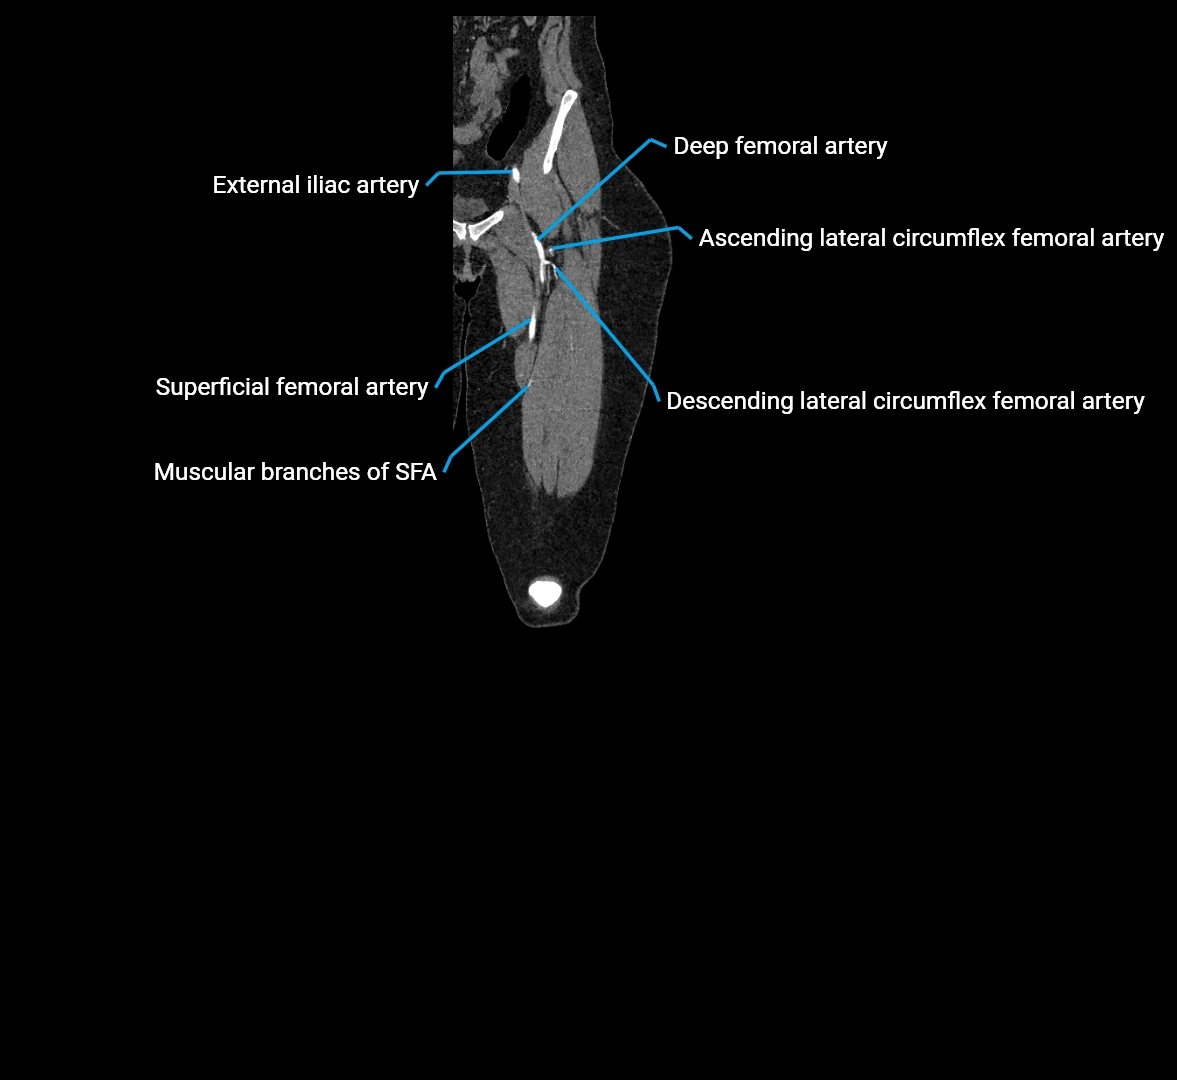

CT images

image